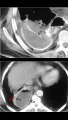

Chest and Pleura, Pleural cavity